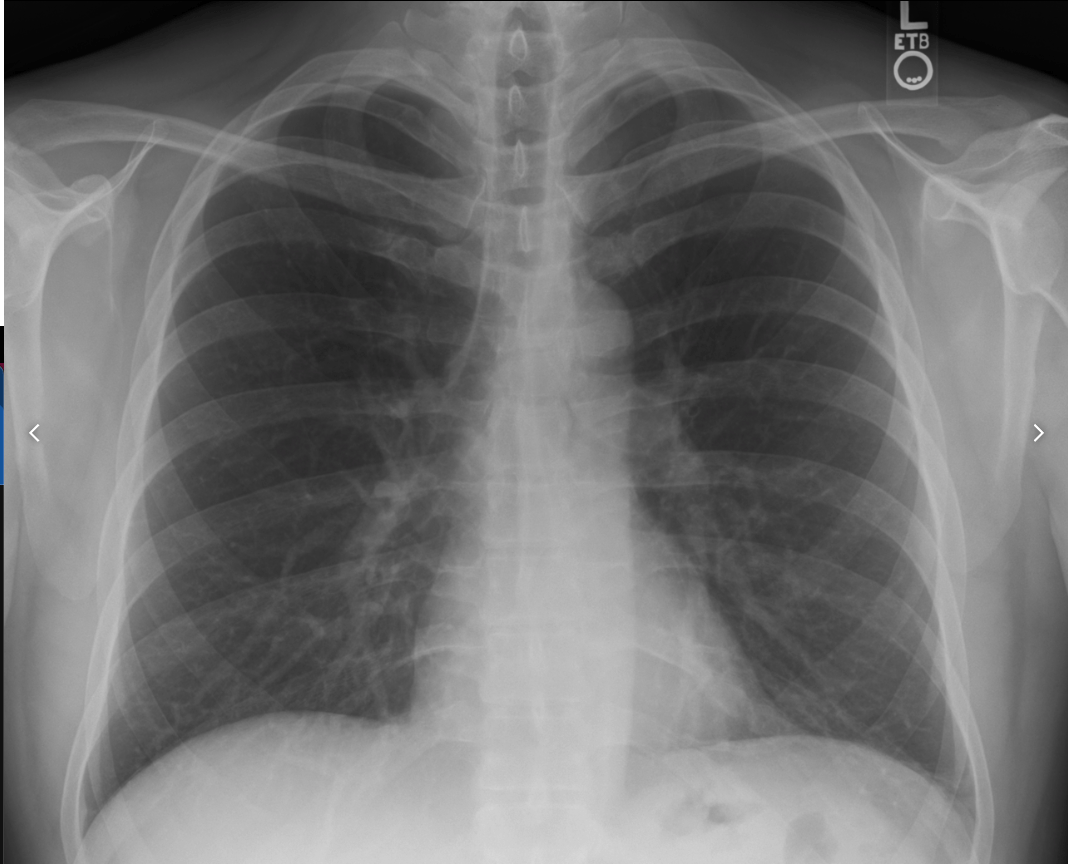

• Lets take this image for example.

• What do we see in it?